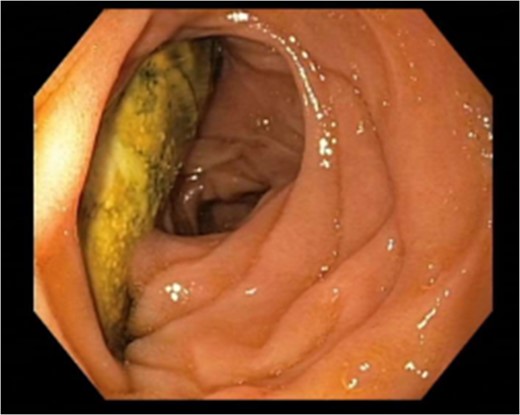

In December 2013, she was admitted with melena. Gastroscopy, CTA and sigmoidoscopy did not identify the bleeding source. The hemorrhage stopped spontaneously. Readmission occurred 2 weeks later due to hypovolemic shock. Endoscopic ultrasound revealed an aortoenteric fistula with a 3 × 2 cm2 opening with exposure of aortic graft material. Open surgery was considered too risky and a new stentgraft (Endurant®, Medtronic) was implanted in January 2014. For the next 2 years there were several admissions due to sepsis. In 2016, the patient was admitted due to hematemesis. Endoscopy visualized aortic graft material penetrating the duodenal wall (Fig. 2). The patient was stabilized and was discharged to her home.

Endoscopy performed November 2016 revealing breakthrough of aortic graft material into the last part of the duodenum.

Regarding curative surgery, there are two main methods. (i) In situ graft replacement using an antibiotic-soaked prosthesis, a silver prosthesis or a lower extremity vein graft restores circulation of the lower body and avoids leaving a closed aortic stump which carries a risk of blowout. (ii) Implantation of an axillofemoral bypass to maintain circulation of the lower limbs followed by aortic graft excision, leaving a closed infrarenal aortic stump. The second method has limited long-term patency but avoids lower limb ischemia during surgery, thereby decreasing operative risk. Our patient had significant risk factors at the time of diagnosis and it was therefore decided to refrain from graft explantation. Stentgrafts can reduce immediate risk, acting as bridging therapy in inaccessible areas, active bleeding and high-risk patients, as in this case. Subsequently, the aortoenteric fistula recurred and was treated with another stentgraft in 2014. It recurred once again in 2016 (Fig. 2) to be left to conservative treatment only.